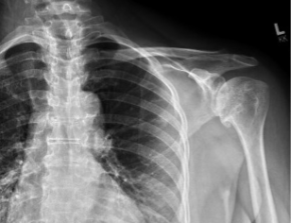

BH is a right hand dominant 70-year-old female, who is retired and moderately active. She presents with 8 months of progressively worsening left shoulder pain affecting her ADLS, sleep and recreational activities. She is 10 years s/p a right anatomic total shoulder arthroplasty. Radiographs and advanced imaging reveal glenohumeral joint advanced degenerative joint disease with an intact rotator cuff. Preoperative planning reveals a native 3 degrees of retroversion with 0 degrees of inclination. As she was extremely happy with the fully functional contralateral shoulder she has enjoyed for the past decade, she was interested in the same solution – an anatomic total shoulder arthroplasty.